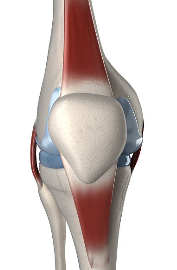

무릎 안쪽 통증 원인 대표적인 9가지와 셀프 마사지 방법에 대해서 알아보겠습니다.무릎은 우리 몸의 중요한 관절 중 하나로, 걷기, 뛰기, 앉기 등 다양한 움직임에 참여합니다. 하지만 무릎에 과도한 부담이 가해지거나 외부 충격이 가해지면 무릎 안쪽에 통증이 발생할 수 있습니다.

무릎 안쪽 통증은 단순한 근육통일 수도 있지만, 심각한 질환의 증상일 수도 있으므로 주의해야 합니다. 무릎 안쪽 통증은 무릎 관절이나 인대, 연골, 근육 등의 손상이나 염증 때문에 발생할 수 있습니다. 무릎 안쪽 통증의 원인은 다양하지만, 대표적으로 9가지를 알아보겠습니다.